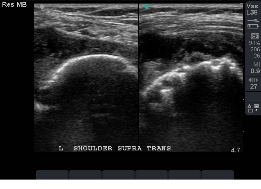

Pathological Shoulder Images